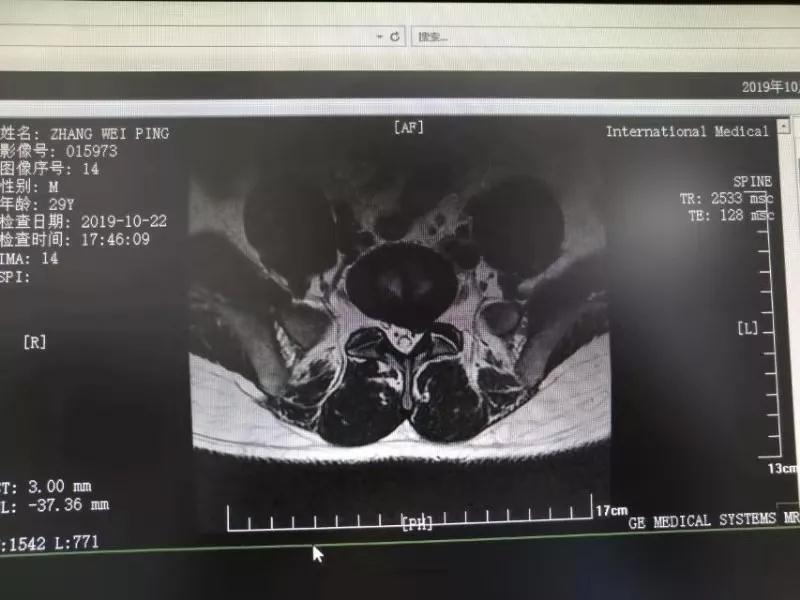

10月25日,29歲的患者小張了解到西安國(guó)際醫(yī)學(xué)中心骨科醫(yī)院專家云集,一大早便在家人的陪同下,來(lái)到西安國(guó)際醫(yī)學(xué)中心骨科醫(yī)院就診?!拔已闯掷m(xù)2年多,最近感冒后腰痛癥狀明顯加重了。”小張面露苦楚,因?yàn)殚L(zhǎng)期腰痛、左下肢放射性疼痛,她晚上睡覺(jué)不能平躺,經(jīng)常疼得睡不著,需要口服止痛藥物才能有所緩解。走路走不了多遠(yuǎn)就開(kāi)始腿抽的疼,嚴(yán)重影響到工作和生活。

結(jié)合患者的檢查以及年齡情況,王自立副院長(zhǎng)推薦讓專門(mén)研究椎間孔鏡技術(shù)王雄勛主任給小張做微創(chuàng)的椎間孔鏡手術(shù)。該手術(shù)創(chuàng)傷很小,不影響脊柱的穩(wěn)定性,尤其適合于椎間盤(pán)突出的年輕患者,懷著對(duì)骨科醫(yī)院專家的信任,小張與家人商議后,接受手術(shù)治療。